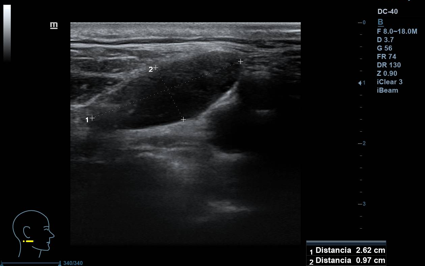

Lesión hipoecogénica cervical de aspecto sólido, de 2,5 x 1 cm (ancho x alto), con hilio vascular que preserva, impresiona de residual, vascularizado (Doppler). Otras lesiones similares de menor tamaño, pero con hilio mejor preservado, de aspecto benigno. Todas las lesiones impresionan de adenopatías. A nivel contralateral: lesiones similares en menor cuantía, también de aspecto benigno. Tiroides normal.